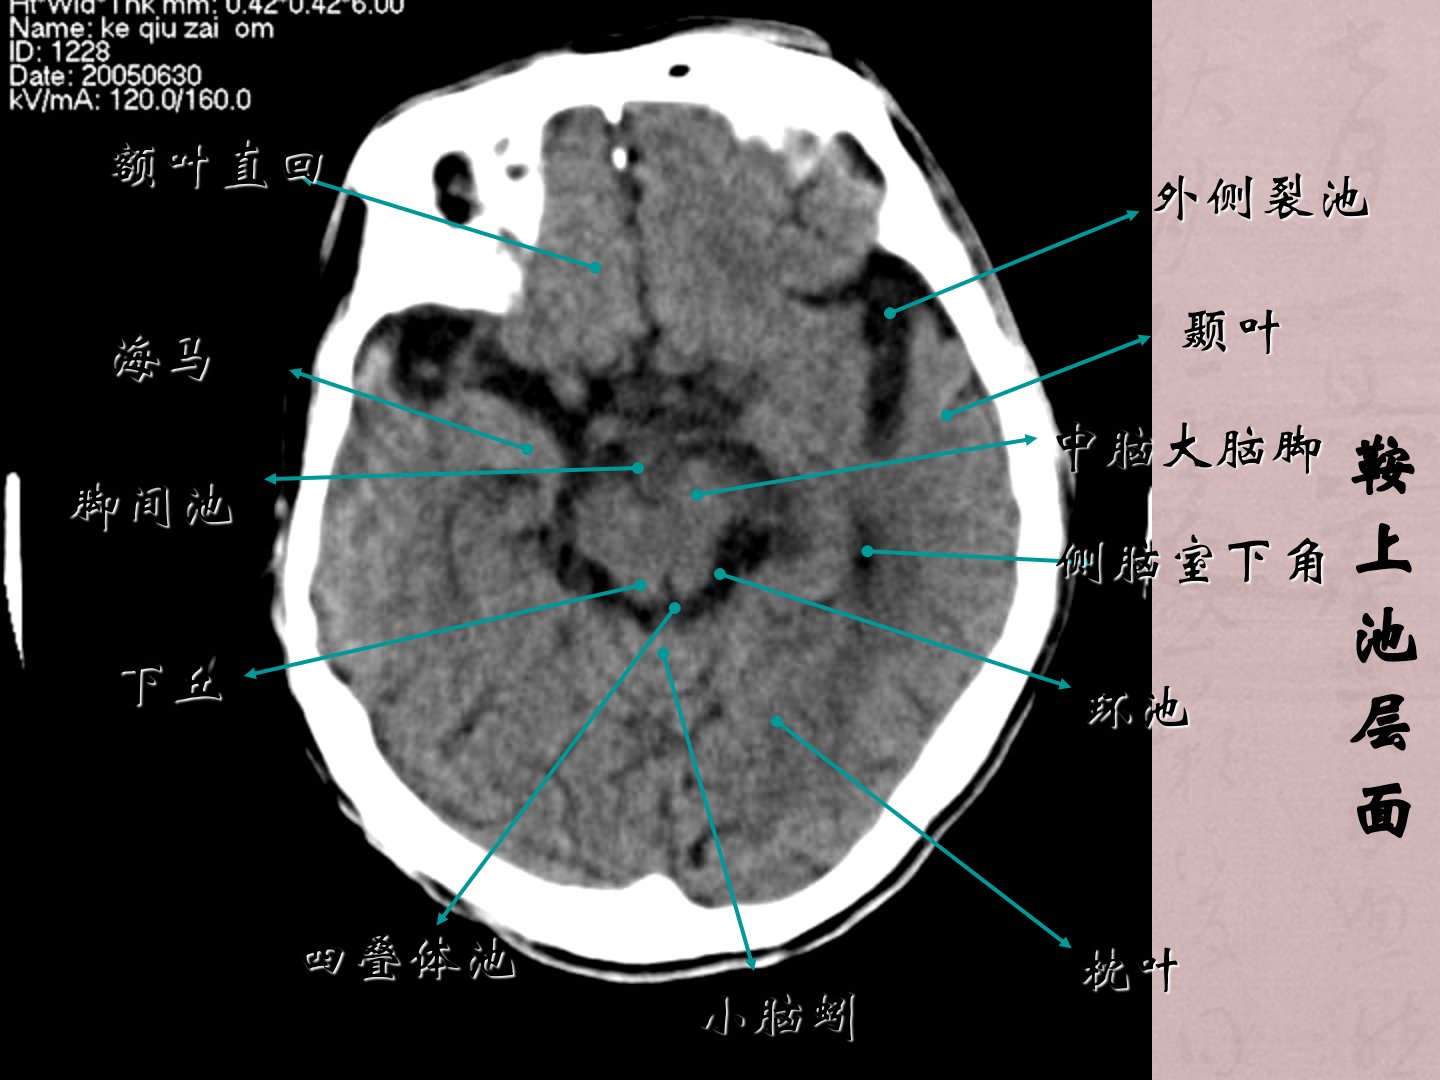

一颅脑基本解剖二常见疾病(1)脑血管病(2)颅脑外伤(3)颅内肿瘤性病变(4)颅内感染性病变、蝶窦顶部层面筛窦桥脑小脑中脚小脑蚓小脑半球第四脑室海绵窦颞叶桥小脑角池蝶窦乙状窦基底动脉视神经小脑延髓池鞍上池层面中脑大脑脚外侧裂池额叶直回四叠体池海马环池枕叶脚间池颞叶侧脑室下角小脑蚓下丘第三脑室下部层面额叶纵隔裂侧脑室前角第三脑室上丘四叠体池松果体(钙化)外侧裂池枕叶丘脑岛叶侧脑室后角尾状核头第三脑室上部层面大脑镰额叶胼胝体膝部尾状核头部侧脑室前角透明隔穹窿部丘脑室间孔中间帆池脉络丛外侧裂池枕叶侧脑室三角区视辐射内囊前肢内囊后肢侧脑室体部层面颞叶侧脑室体部放射冠额叶胼胝体压部上矢状窦枕叶胼胝体膝部...